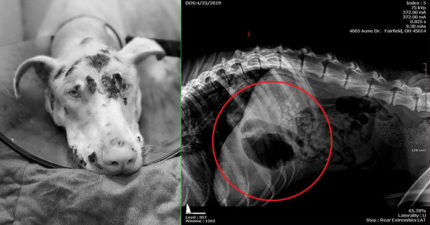

無良飼主「餓死愛犬」被判刑 照X光「裝滿巨石」網友:換他吃